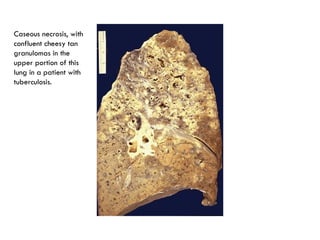

Caseous necrosis, with

confluent cheesy tan

granulomas in the

upper portion of this

lung in a patient with

tuberculosis.

Caseous Necrosis

 Found in the center of foci of tubercular infection it has combine

features of both above necrosis.

 Appearance-

Grossly-

Dry cheese & soft granular & white appearance partly

attributed to histotoxic effect of lipopolyscchariedes present in

capsule of tubercle bacilli.

Microscopically-

Foci are eosinophilic structureless & contain granular debris.

Surrounding tissue shows inflammatory reaction consisting of

epitheloid cells with interspersed giant cells of langerhans &

foreign body & peripheral mantle of lymphocytes.